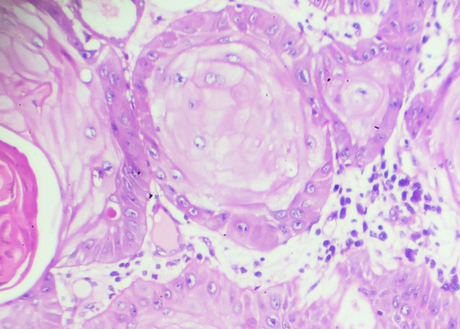

An image of chronic lymphocytic leukemia cells under a microscope